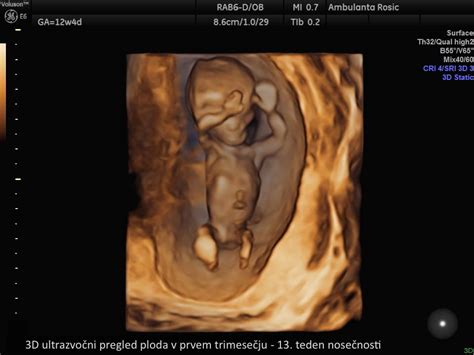

Na začetku drugega trimesečja, okoli 13. tedna, plod meri približno 7,5 cm in tehta okoli 30 gramov. V tem obdobju se organi in tkiva, ki so se oblikovali v prvem trimesečju, začnejo intenzivno razvijati. Črevo, ki je bilo sprva del popkovine, najde svoje mesto v dojenčkovem trebuhu. Razvijata se jezik in glasilke, ušesa so že na svojem mestu, glava pa predstavlja še vedno polovico telesne velikosti. Kožo začno prekrivati tanke dlačice, imenovane lanugo, ki pomagajo pri uravnavanju telesne temperature dojenčka. Pomembna novost je tudi proizvodnja inzulina v trebušni slinavki, ki bo kasneje pomemben za uravnavanje krvnega sladkorja.

Sredi trimesečja, okoli 20. tedna, ko je polovica nosečnosti že mimo, plod meri že okoli 16,4 cm in tehta približno 260 gramov. V tem času so notranji organi že na svojem mestu, kar omogoča izvedbo ultrazvočnega pregleda morfologije ploda, ki natančno oceni njegov razvoj. Večina nosečnic na tem pregledu izve tudi spol svojega otroka. Do konca drugega trimesečja, okoli 26. tedna, otrok meri že približno 35 cm in tehta med 1 in 2 kg. Njegovi organi se še naprej razvijajo, slušni aparat je že dobro razvit, začnejo rasti obrvi, nohti pa segajo do vrhov prstkov.

V drugem trimesečju nosečnosti se opravijo rutinski pregledi. Okoli 20. tedna poteka ultrazvočni pregled morfologije ploda, med 20. in 28. tednom pa se običajno opravijo analize krvne slike in urina, test na toksoplazmo ter test na nosečnostno sladkorno bolezen. Ti pregledi omogočajo spremljanje zdravstvenega stanja matere in otroka ter pravočasno odkrivanje morebitnih težav.